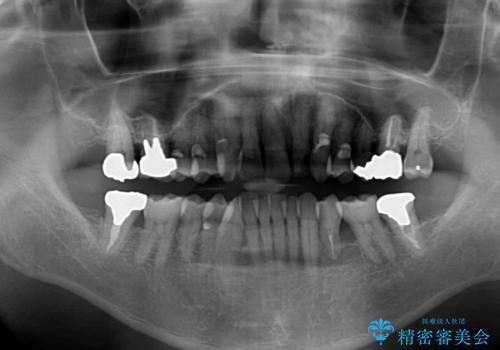

- 上の前歯が痛むとのことで来院された患者様です。

検査を行ったところ、前歯1本は周辺の骨が失われており、抜歯が必要でした。

上顎の奥歯は全体的に歯周ポケットが散見され出血が認められたため、歯周外科処置を行うこととしました。

また、前歯の部分矯正も希望されたため、歯周外科処置と平行して矯正治療を行うこととしました。